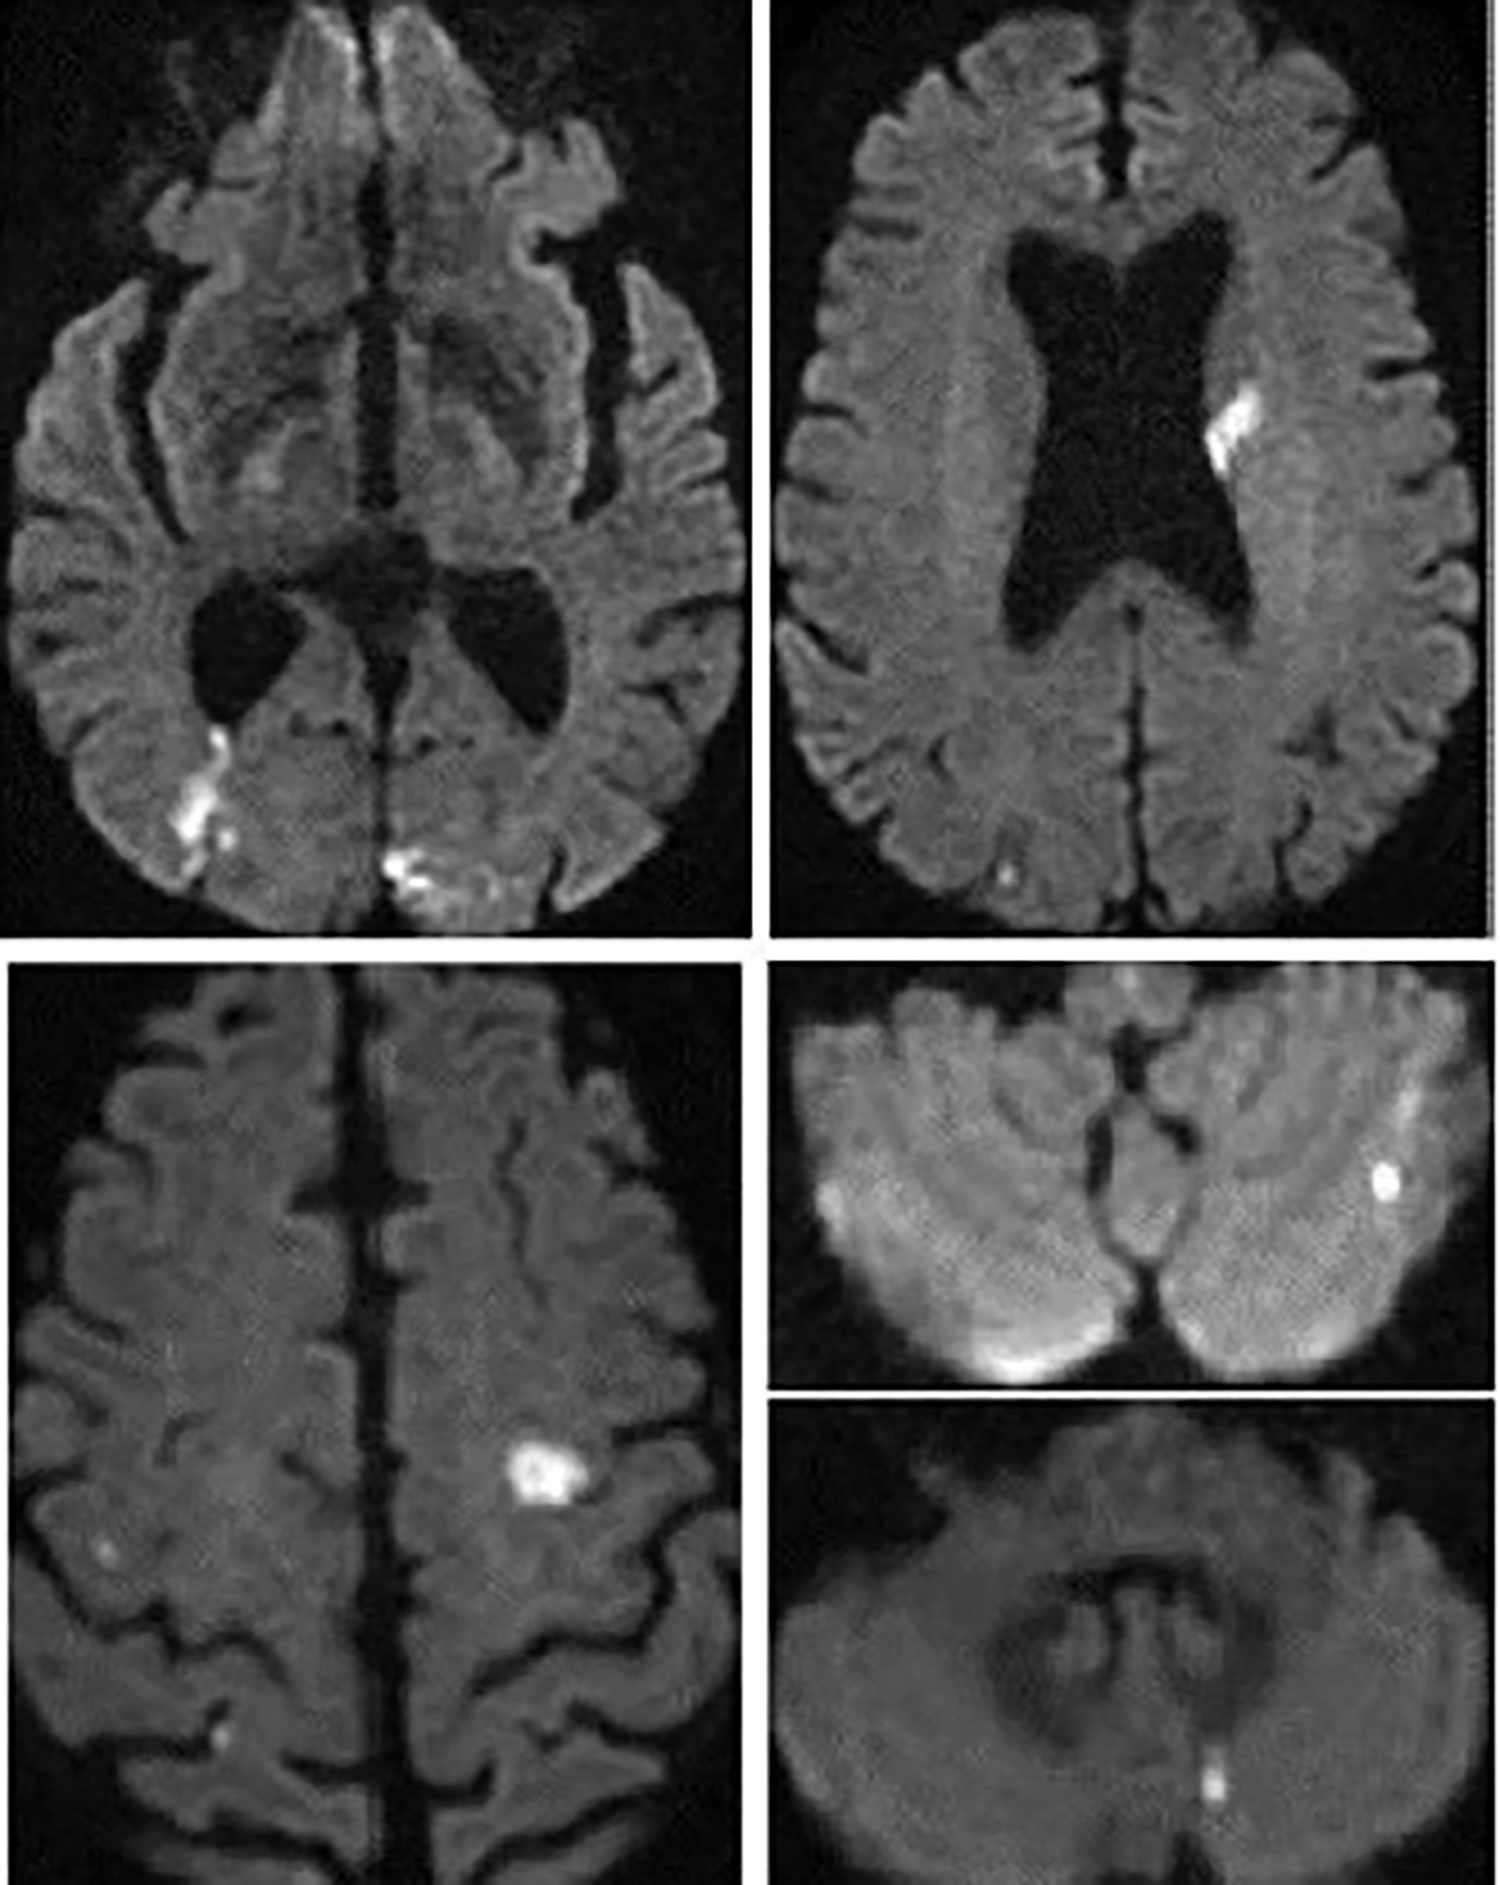

Figure 4

Cerebal MRI diffusion sequence from patient no.1 showing multiple supra- and infra-tentorial ischemic foci.

Figure 8

Cerebral MRI diffusion sequence in patient no. 2 showing multiple supra- and infra-tentorial ischemic foci.